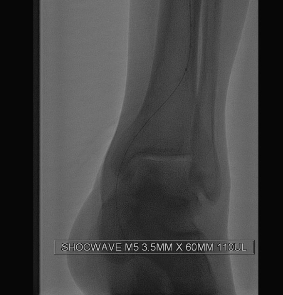

أشار إلى أن التدخل النوعي باستخدام تقنية ”بالون الموجات التصادمية“ أتاح للفريق الطبي تفتيت التكلسات الصلبة داخل الشرايين بدقة وفعالية، ونجح في استعادة تدفق الدم بشكل طبيعي إلى الطرف، مما يعزز بشكل كبير فرص التئام الجروح وتجنب خيار البتر.

أكد الدكتور الثويمر أن هذه التقنية تُعد من أحدث الحلول العلاجية المعتمدة عالميًا، حيث تعتمد على إطلاق موجات تصادمية دقيقة تعمل على توسعة الشرايين المتكلسة بأمان، دون التسبب في أضرار لجدران الأوعية الدموية المحيطة.